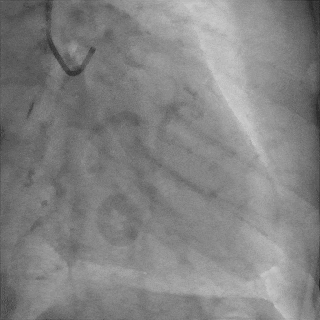

双侧造影,观察闭塞起始位置、长度、走行等

尝试通过RCA-圆锥支侧枝逆向开通LAD :

微导管辅助下,用SUOH03导丝尝试送入侧枝

经微导管TIP injection可见侧枝重度迂曲

侧枝重度迂曲,反复尝试未能通过